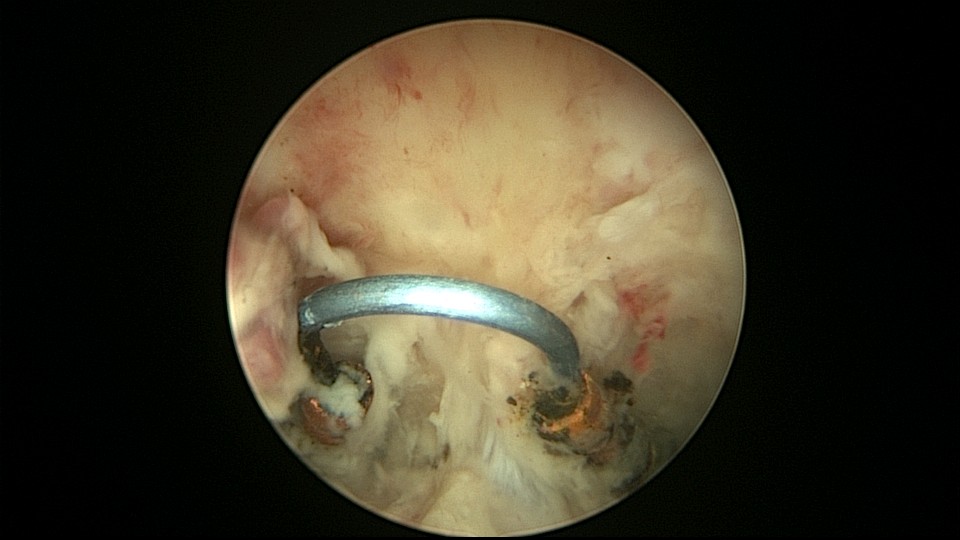

患者48岁,G3P1,顺产1次。安环10年,绝经1年,外院取环失败,子宫穿孔,腹部平片无异常。宫腔镜见宫腔广泛致密粘连,V型环与粘连组织嵌顿,取环钩盲视下多次尝试钩取节育环,均失败。取环钩循镜鞘外侧进入宫腔,直视下钩住节育环,顺利取出。再次置镜寻找子宫穿孔处并进入盆腔,见网膜脂肪组织,确认无活动性出血及盆腔积血,结束手术。